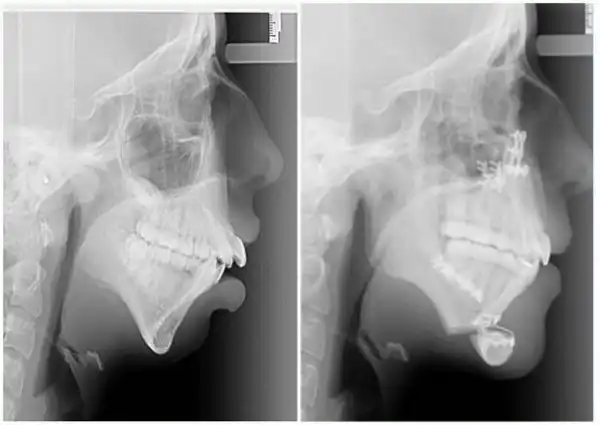

В течение следующих 6 лет Элли посещала челюстно-лицевого хирурга Эмму Вулли из госпиталя Глан Клвид, Британия, изменить не только свою челюсть, но и жизнь. Предлагаем вам взглянуть на фантастические результаты, которых им удалось добиться.

Операция заключалась в вырезании челюсти по горизонтали и вертикали с последующим ещё большим хирургическим вмешательством.

Несмотря на боль от операций, Элли говорит, что в восторге от результатов: "Я почувствовала облегчение, наконец-то я чувствую, что могу быть самой собой. Я была очень застенчивой, но теперь я чувствую себя гораздо увереннее. Это изменило мою жизнь". "Многие люди даже не догадываются о том, что имеют дефект челюсти и думают, что у них есть просто проблемы с прикусом. Если не обратить на это внимание в раннем возрасте, то это может принести реальные трудности в будущем", — сказала хирург Эмма Вулли